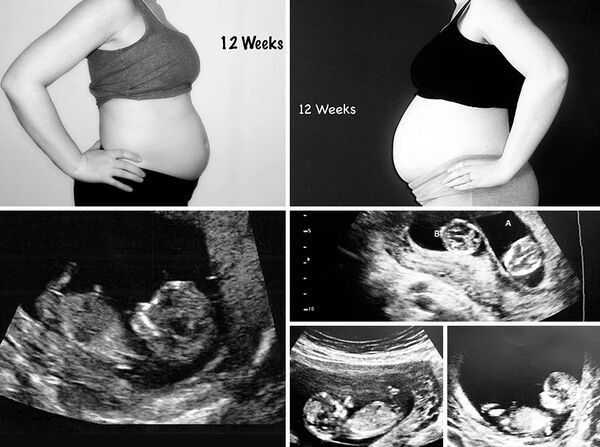

Burda ise Janet 12 haftalık hamile, sağ taraftaki fotoğraf ikizlere ait!